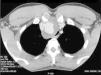

We present the case of a 26-year-old male: a farm worker and non-smoker, with unremarkable medical and family history. He was referred by his family doctor to the pneumology clinic with symptoms of dyspnea progressing over the last 3 years. During that time, he had been treated with beta-agonist inhalers and inhaled corticosteroids for suspicion of bronchial asthma, in spite of which the dyspnea continued to progress, to the point that, in recent months, it has limited his daily activities. The patient had no cough, no expectoration, and no other respiratory symptoms. The only revelation from his medical history was that, 4 years earlier, he had been in a high-speed auto accident in which he suffered closed chest trauma, with no medical consequence of any kind at that time. Physical examination revealed a satisfactory general condition, vital signs within normal range, cardiopulmonary auscultation within normal limits, and oxygen saturation of 98% (fraction of inspired oxygen 21%), the rest of the examination being unremarkable. Simple chest X-ray showed a widening of the upper mediastinum, with compression and displacement of the trachea toward the left. A CT scan of the chest was ordered, which revealed the existence of a 3.5cm×3cm×2.5cm saccular aneurysm of the innominate artery, surrounded by a thick wall (up to 15mm). This wall showed small calcifications in its sinus. The aneurysm was causing severe compression of the trachea and displacing it toward the left side (Fig. 1). Taking the patient's history into consideration, these findings were consistent with a chronic post-traumatic pseudoaneurysm. Flow–volume curves confirmed a fixed extrathoracic obstruction. Regarding laboratory tests, both the haemogram and chemistries were within normal limits; arterial blood gases were also normal.